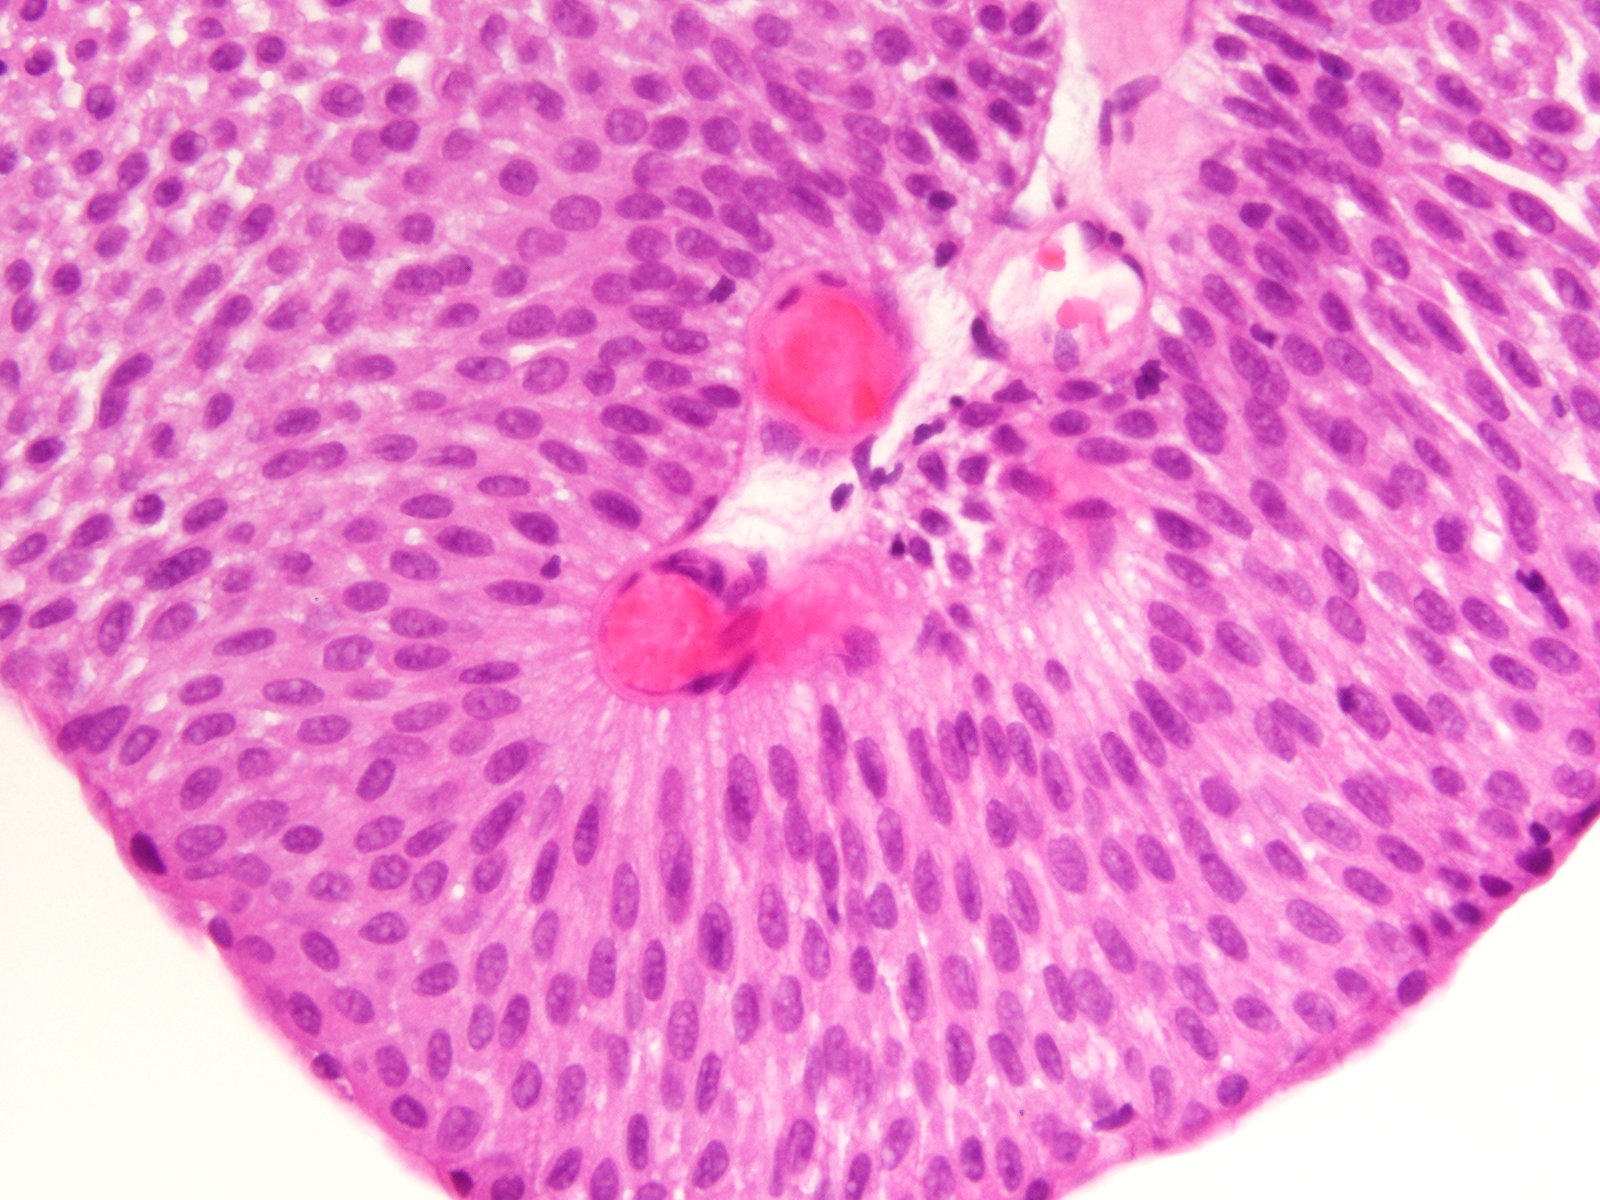

Consensus grade: PUNLMP

87 y/o. Bladder tumor.